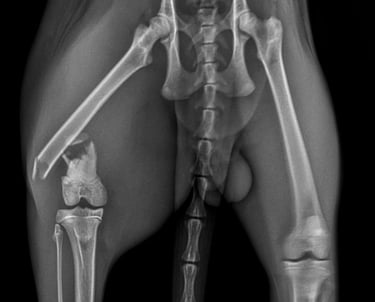

Fracturas complejas

Solución ideal para fracturas con múltiples fragmentos o alta inestabilidad.

Hueso comprometido

Indicado en pacientes con hueso débil, osteoporótico o de baja calidad.

Los sistemas de placa bloqueada ofrecen ventajas significativas frente a métodos tradicionales, ya que combinan estabilidad mecánica con un enfoque más biológico de la reparación ósea.

La fijación entre tornillo y placa crea una estructura rígida que mantiene los fragmentos óseos alineados incluso en fracturas complejas.